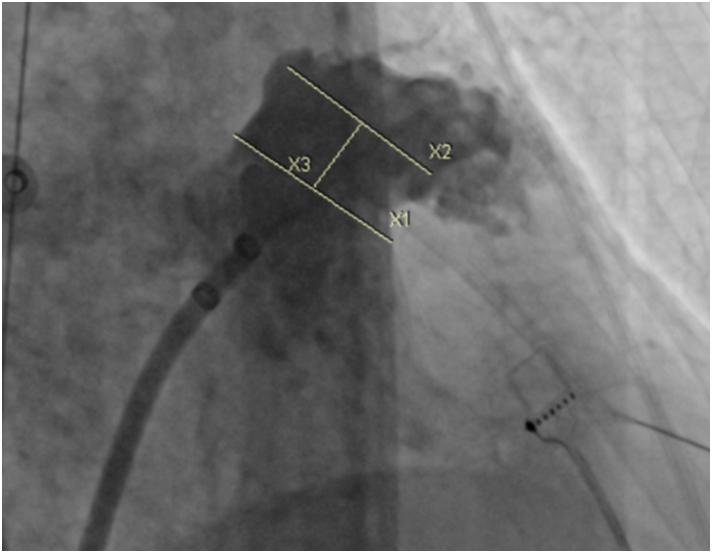

中国是脑卒中高发大国,房颤是脑卒中最重要的病因之一。房颤的治疗目标是恢复窦性心律和预防栓塞事件的发生。据仁济医院宝山分院执行主任黄剑锋教授介绍,接受“一站式”介入治疗的患者72岁高龄,同时合并冠心病和心房颤动,冠脉造影提示三支冠脉病变,临床评估CHA2DS2-VASc评分5分,HASBLED评分4分,是一个同时存在高血栓栓塞和高出血风险的患者。在术前积极完善各项辅助检查,评估患者的适应症,与患者及家属充分沟通,进行术前讨论,考虑到患者高龄,为减少麻醉意外风险,增加手术耐受程度,最终决定在局部麻醉下实施ICE指导下“经皮左心耳封堵术+射频消融”一站式治疗技术。

什么是左心耳封堵手术?经皮左心耳封堵手术是一项房颤卒中预防的国际先进技术,主要针对合并心房颤动又不宜长期服用抗凝药物的患者,微创治疗,无需开胸,整个手术可在1小时左右完成,成功进行左心耳封堵术可实现“一次植入,终身预防”,从而提高房颤患者生活质量。